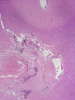

The followings are representative images from autopsy. Panel D to E are taken from the softened area. Panel G and H are taken from the blood vessels of the circle of Willis.